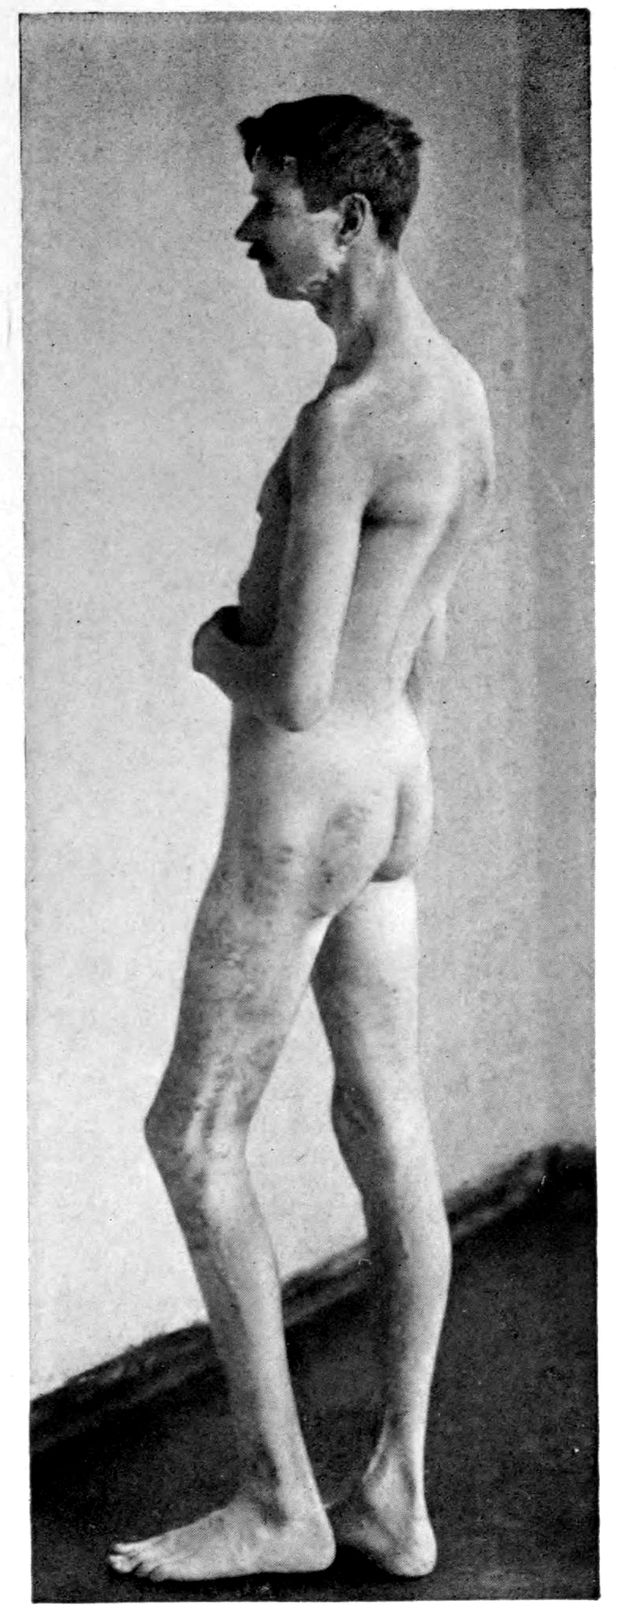

Case 5. John Lawrence was an under-sized negro, who came under hospital observation when he was 23 years of age. There was some evidence that the patient’s father was a neurosyphilitic although accurate data were out of the question. At all events, John had Hutchinsonian teeth, a forward bowing of the tibiae, and Argyll-Robertson pupils. These findings together with a history of backwardness at school seem to stamp the diagnosis. It seems that there had been a change for the worse from the age of 18, though the boy had been able to sell newspapers and black shoes up to within a year of his arrival at the hospital. During the last months of his life, he showed a general incoördination, with false movements suggesting those of a drunken person. There were numerous tremors, the glance was shifting, and there was a tendency to nystagmus. Some of these phenomena (taking into account that the Hutchinsonian teeth were not entirely typical and there was even at times some doubt as to whether the pupils were actually stiff) led to a question of the diagnosis multiple sclerosis.